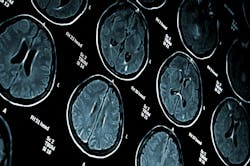

Black patients underwent medical imaging for cognitive impairment years later than white and Hispanic patients and were less frequently tested with MRI, according to research being presented this week at the annual meeting of the Radiological Society of North America (RSNA).

Medical imaging—ideally with MRI—plays an increasingly important role in the diagnostic work-up of cognitive impairment. However, it is unknown how disparities in imaging access may lead to these delays in cognitive impairment diagnoses.